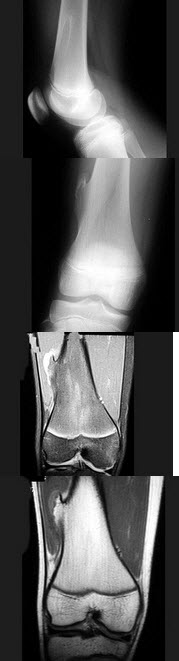

76、单项选择题

男,13岁,运动后膝关节疼痛,结合图像,最可能的诊断是()

A.正常影像

B.动脉瘤样骨囊肿

C.骨软骨瘤

D.成骨细胞瘤

E.骨样骨瘤